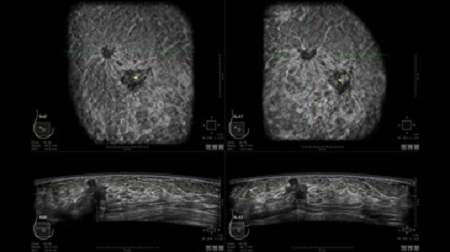

GE INVENIA ABUS – это современный УЗИ аппарат, который создан для точной и эффективной диагностики сканирования с высокой плотностью молочных желез. Выявляемость патологий раковых и предраковых стадий заболевания составляет 55%, что в конечном счете позволяет ставить врачу точные и своевременные диагнозы. Традиционные методы использования маммографии не показывают такой выявляемости, ограничиваясь лишь 3-38%.

УЗИ-аппарат GE INVENIA ABUS позволяет проводить максимально операторонезависимые процедуры, что значительно снижает риск неправильной постановки диагноза и сопутствующие издержки на обработку информации. Система готовит отчет в течение 3-х минут после сканирования, это безусловное преимущество по сравнению с обычным УЗИ сканером.

• Получение объемных 3D изображений с возможностью покадрового просмотра

• Отображение объемных 3D ультразвуковых изображений, которые состоят из традиционных поперечных и воссозданных коронарных и сагиттальных проекций

• Многооконный просмотр: 4 - 12 изображений

• Стандартизованная ориентация изображения: «толстый срез» в коронарной плоскости; поперечная; сагиттальная плоскость; радиальный и антирадиальный поворот изображения; просмотр исключительно области интереса

• Одновременный просмотр двух изображений для сопоставления в коронарной плоскости